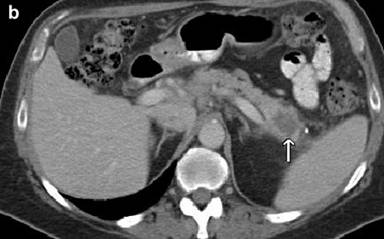

On follow-up in May 2012, the patient reported feeling generally well, except for a new onset of abdominal discomfort, occurring 30 minutes after eating, lasting for 30-60 minutes and associated with diarrhea. He did not complain of other new symptoms. A PET/CT after eight cycles of chemotherapy indicated a near-complete disappearance of the disease at the level of spleen and lymph nodes, but a new mass at the tail of the pancreas measuring 2.0x2.5 cm (Figure 2). Several small (5 mm) hypodense lesions were noted in the liver. These findings were not present on the PET/CT done after the sixth cycle of chemotherapy. To evaluate the focal area of persistent uptake in the pancreatic tail, a CT scan was done in June 2012. It confirmed the mass in the tail of the pancreas, highly suspicious for malignancy (Figure 3). His anemia and thrombocytopenia remained stable. The white blood cell count was within normal range, but showed persistently decreased absolute lymphocyte count. Serum IgG and IgM immunoglobulin levels were decreased to 642 mg/dL (reference range: 782-1,195 mg/dL) and 31 mg/dL (reference range: 53-334 mg/dL), respectively. Serum IgA was normal. CA 19-9 level was elevated at of 1,177 U/mL (reference range: 0-30 U/mL). Biopsy of the pancreatic mass revealed poorly differentiated adenocarcinoma (Figure 4). Immunohistochemical stains of the biopsy specimen revealed positive pankeratin, CK7, CA 19-9, BerEP4, CEA and p63 markers, suggesting primary adenocarcinoma of the pancreas. The patient was considered for possible distal pancreatectomy. However, a preoperative laparoscopic exam showed multiple liver and peritoneal tumor implants, with a biopsy showing pancreatic adenocarcinoma (Figure 4). In addition, the liver biopsy revealed an adjacent atypical lymphoid infiltrate consistent with the patient’s previous mantle cell lymphoma, staining positive for CD20, CD5, BCL-2 and cyclin D1 (Figure 4). The close proximity of the metastatic pancreatic cancer lesions and the mantle cell lymphoma infiltrate was consistent with collision tumors in the hepatic parenchyma (Figure 4).

Figure 3. The coronal (a.) and axial (b.) CT scan views demonstrating a mass in the tail of the pancreas (arrow) characteristic of a pancreatic adenocarcinoma. |